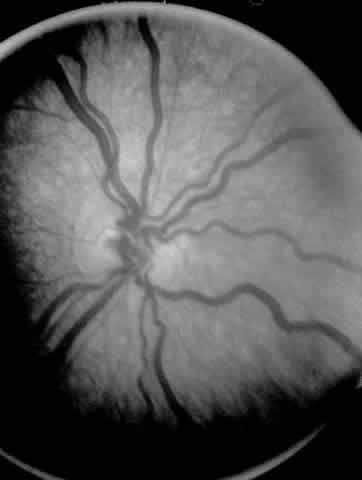

ROP accounts for a large number of retinal detachments in the pediatric

population. The International Classification of Retinopathy of Prematurity

helped greatly to improve communication about, and consequently

treatment of, ROP. It describes affected eyes in terms of stage, zone, and

absence or presence of plus disease18 (Figs. 1, 2, and 3). Screening of premature infants is an important feature in the care of

ROP, which is perhaps the most significant and enduring finding of the

Cryotherapy for Retinopathy of Prematurity Study (Cryo-ROP Study).19

Although several screening protocols have been suggested, we have found that children whose birth weight was 1500 g or less should be screened initially at 4 to 6 weeks after birth, and then every 2 weeks until they reach retinal vascular maturity, which is when nasal vessels in the horizontal meridian have grown to within 1 disc diameter of the ora serrata. During that time, if a child shows threshold disease as defined by the Cryo-ROP Study, namely five clock-hours of contiguous or eight clock-hours of discontiguous neovascularization (stage 3 ROP with plus disease), it is recommended that the child have peripheral ablation with either cryotherapy or laser treatment.19 Newer studies have suggested that zone 1 children may require earlier peripheral ablation.20 The child who fails to respond to peripheral ablation may require further surgical intervention. Two large series reported that scleral buckling for stages 4A and 4B retinal detachments resulted in a retinal reattachment rate of approximately 70%.21,22 These studies were both retrospective; however, they did show a strong trend toward a higher reattachment rate with scleral buckling than the natural history of these detachments, which have a 55% chance of progression of retinal detachment from stage 4 to stage 5 ROP.23 When first assessing a child's retinal detachment, one must judge the amount of effusive versus tractional detachment (Figs. 4 and 5). Scleral buckling would be considered for the child who shows a predominately effusive stage 4B detachment as opposed to a stage 4 predominately tractional detachment, for which lens-sparing vitrectomy may be recommended.24 For a child who has a great deal of retrolenticular touch, lensectomy/ vitrectomy and membrane peeling would be recommended. It appears that the “window” for lens-sparing vitrectomy may be rather brief. In one series, the postconceptual age of the lens-sparing vitrectomized eyes was 42.6 weeks, as opposed to 46.9 weeks for eyes that needed lensectomy/vitrectomy and membrane peeling. This small time difference in the postconceptual age shows the often rapid evolution of this detachment from one in which the lens is salvageable to one in which the lens is unsalvageable. This highlights the need for timely screening of eyes, identification of eyes with progressive disease, and rapid intervention.25